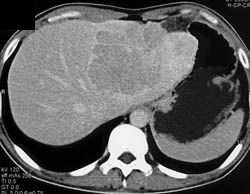

Dilated Common Bile Duct (CBD)